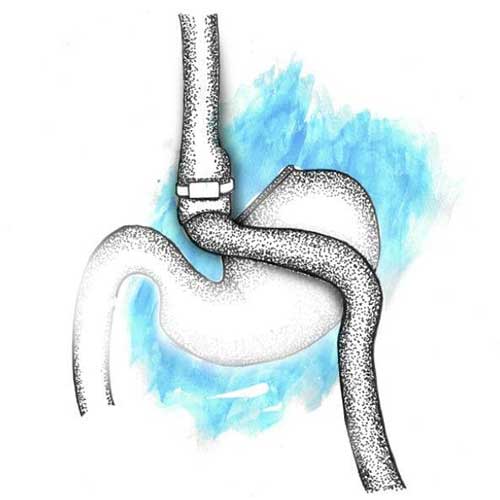

Laparoscopic banded gastric bypass is a reversible weight-loss procedure which involves stapling off a section of the stomach, thereby creating a pouch and reducing the stomach size. This allows food to bypass the beginning of the small intestine, which is the duodenum and part of the jejunum. In addition, a silicon ring is placed over the pouch to prevent dilatation of the pouch. Post surgery, your appetite reduces, as you feel satiated with smaller portions of food.

Laparoscopic banded gastric bypass is the procedure of choice for those who have severe acid reflux and/or high cholesterol. Patients who have suffered from diabetes for over 10 years also benefit from this surgery. This is also an excellent procedure to reduce BMI in order to achieve and maintain better weight loss. It may also be recommended to individuals who have persistent acid reflux and/or weight regain after a sleeve gastrectomy.

You will not be able to eat as much as you did prior to the surgery. You must also be careful about the ‘dumping syndrome’ that occurs in some patients post the surgery. This is when food passes too quickly into the intestine, causing nausea, cramping, bloating, dizziness, etc. Generally, it is triggered by eating high-calorie foods such as sweets and certain carbohydrate sources. This procedure also requires compliance with lifelong supplementation. In extremely rare cases, constant overeating can cause the silicon ring to enter the stomach, necessitating an endoscopy for its removal.